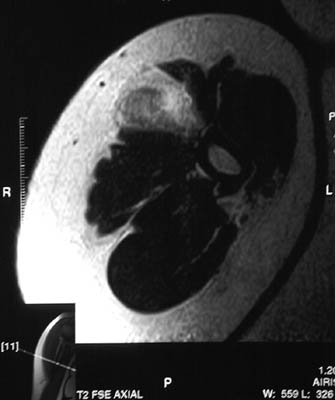

| This axial T2 weighted MRI scan shows a rounded tumor-like mass that is an area of myositis ossificans in skeletal muscle adjacent to the humerus. There is a central core of exuberant granulation tissue surrounded by a zone of reactive bone formation. The lesion appears as a discrete "hot spot" in soft tissue in the bone scan below. |